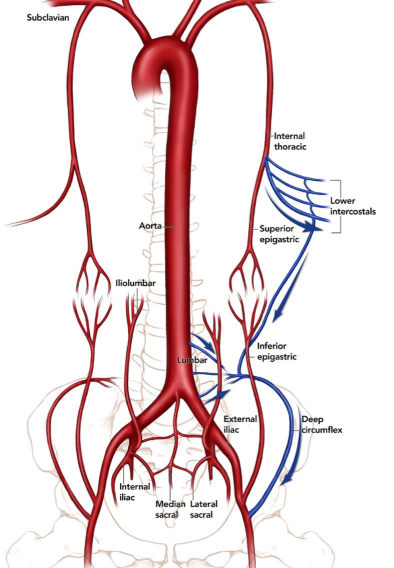

Collatérale de Winslow

- Voie de dérivation lors d’occlusion de l’artère iliaque externe

- Entre l’artère épigastrique supérieure et inférieure

- Subclavière → Mammaire interne → Epg-Sup → Epg-Inf → Iliaque Ext

Collatérale Paralombaires → Artère Circonflexe Iliaque Profonde / Iliaque Interne